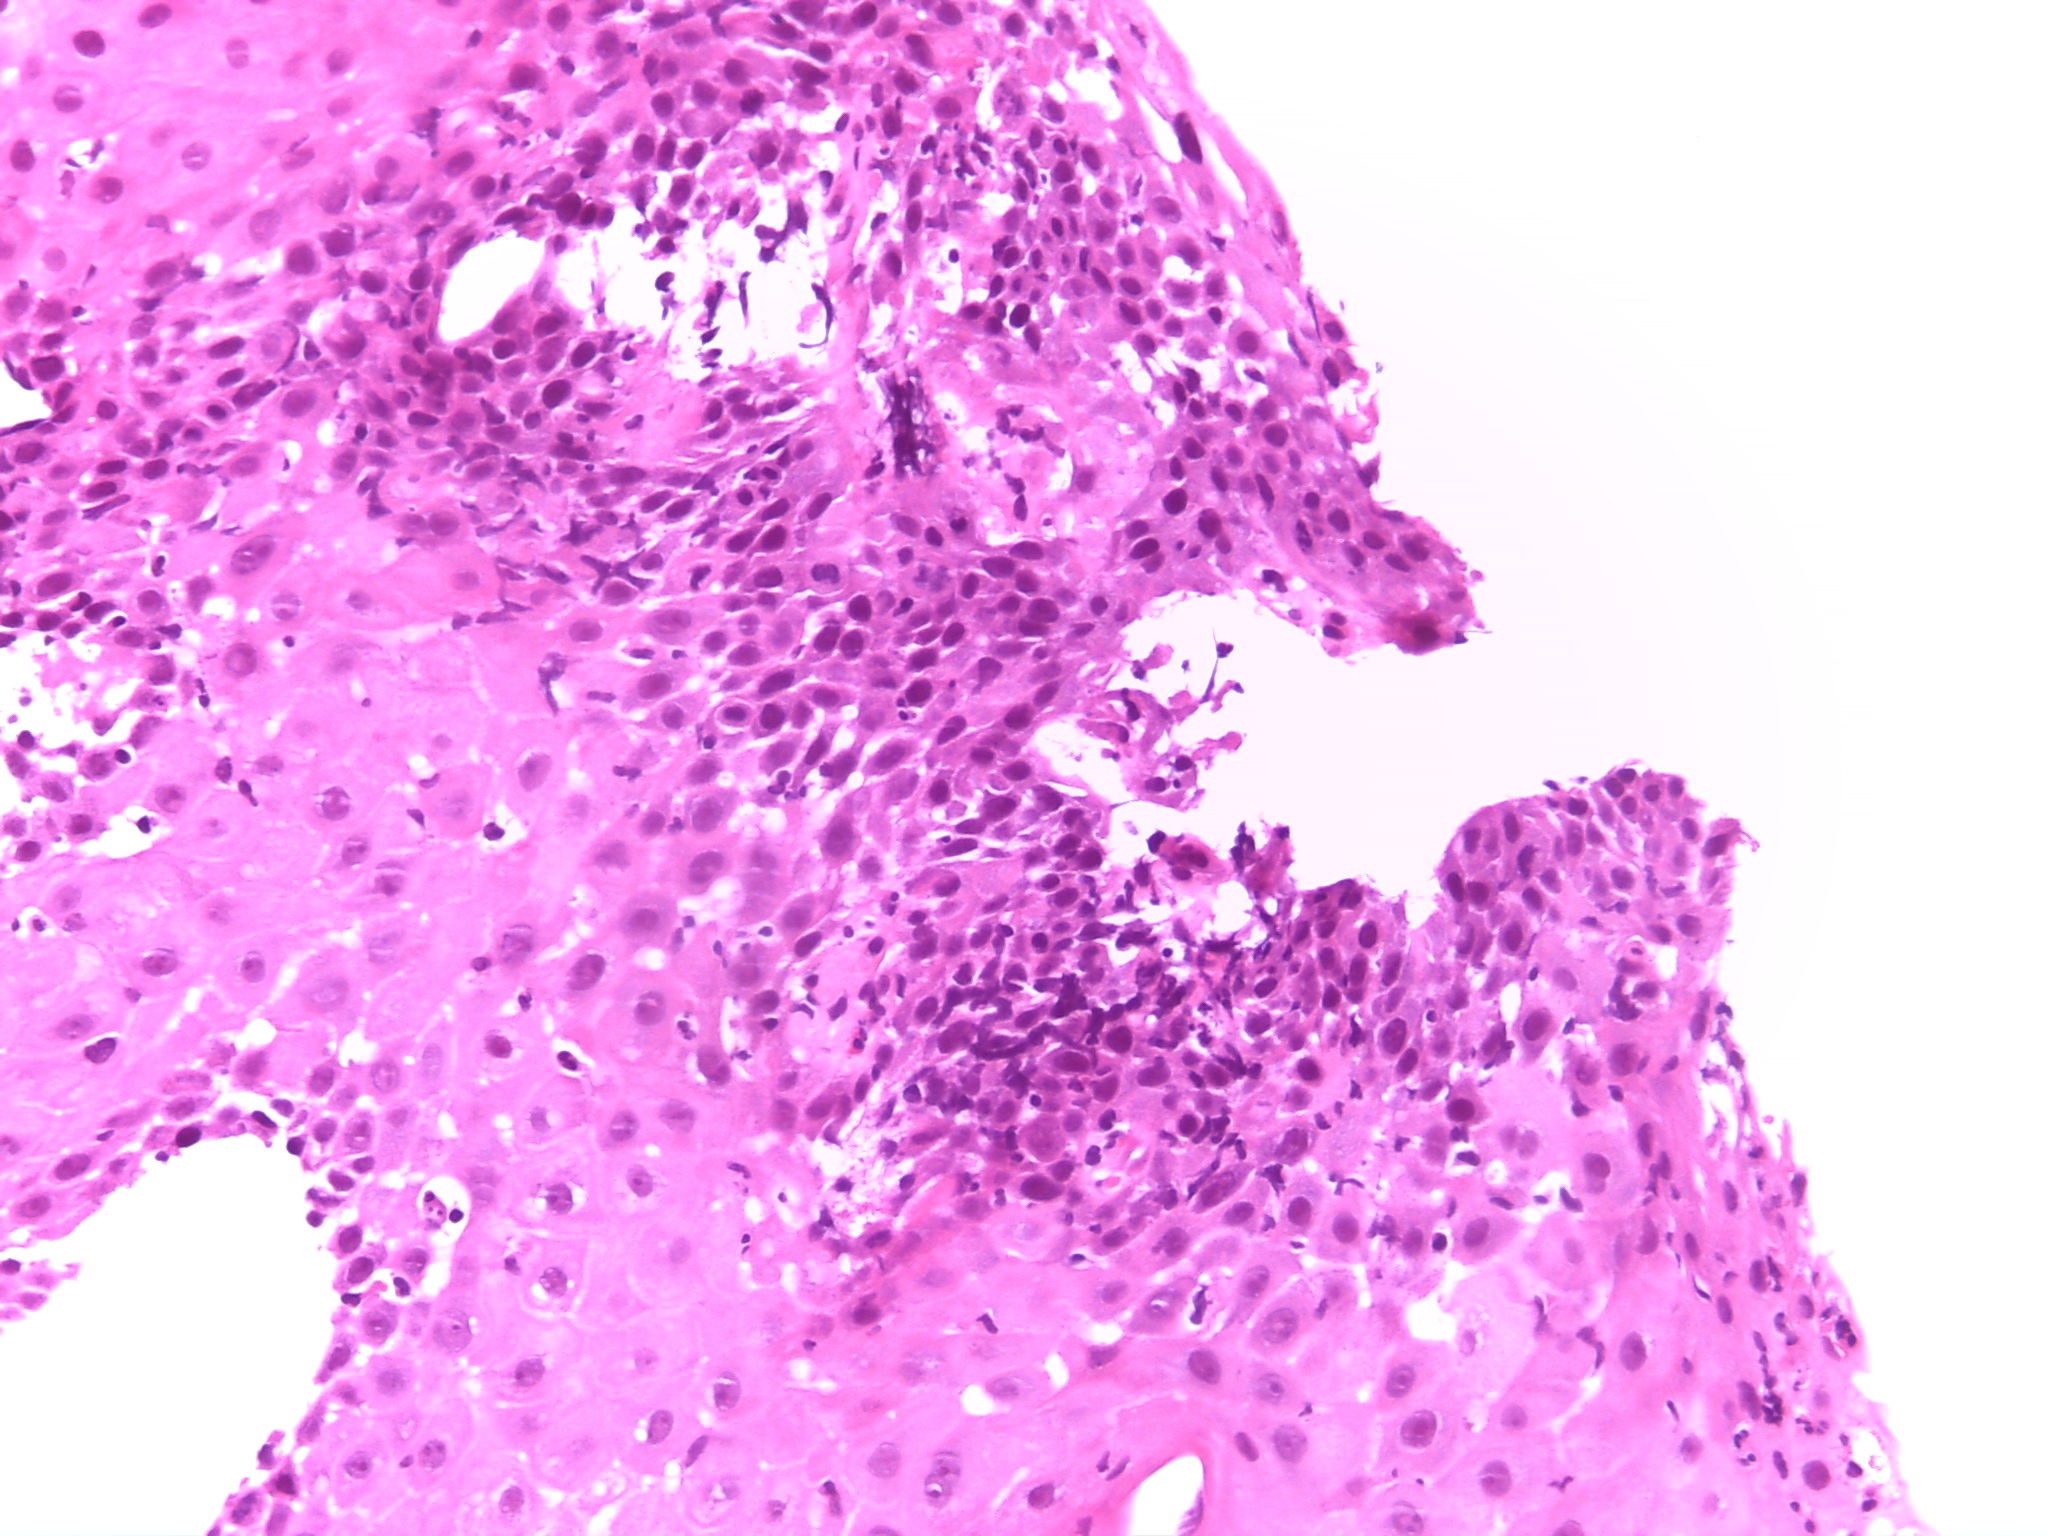

Anatomía patológica informa de que a nivel microscópico se observan focos de cambios reparativos adyacentes a la úlcera y zonas con erosión superficial que presentan un marcado infiltrado inflamatorio intraepitelial de carácter agudo compuesto por eosinófilos y neutrófilos que orienta a un cuadro de esofagitis de etiología viral o fúngica.